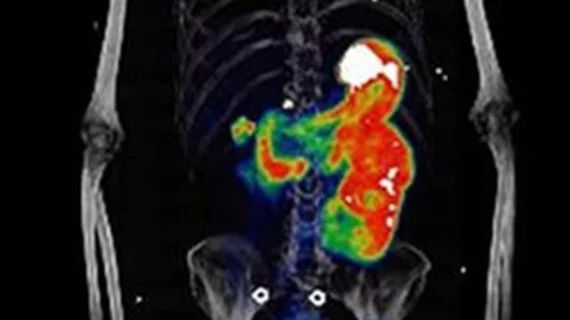

![2-[18F]FDG PET/CT parameters associated with WHO/ISUP grade in clear ...](https://www.researchgate.net/publication/343757008/figure/fig4/AS:941394646532127@1601457382875/The-axial-images-from-left-to-right-are-contrast-enhanced-CT-plain-CT-PET-and-PET-CT_Q320.jpg)